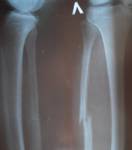

после.jpg

сняли гипс... кость срослась...Просмотров: 3041Комментариев: 10 _Jeff_